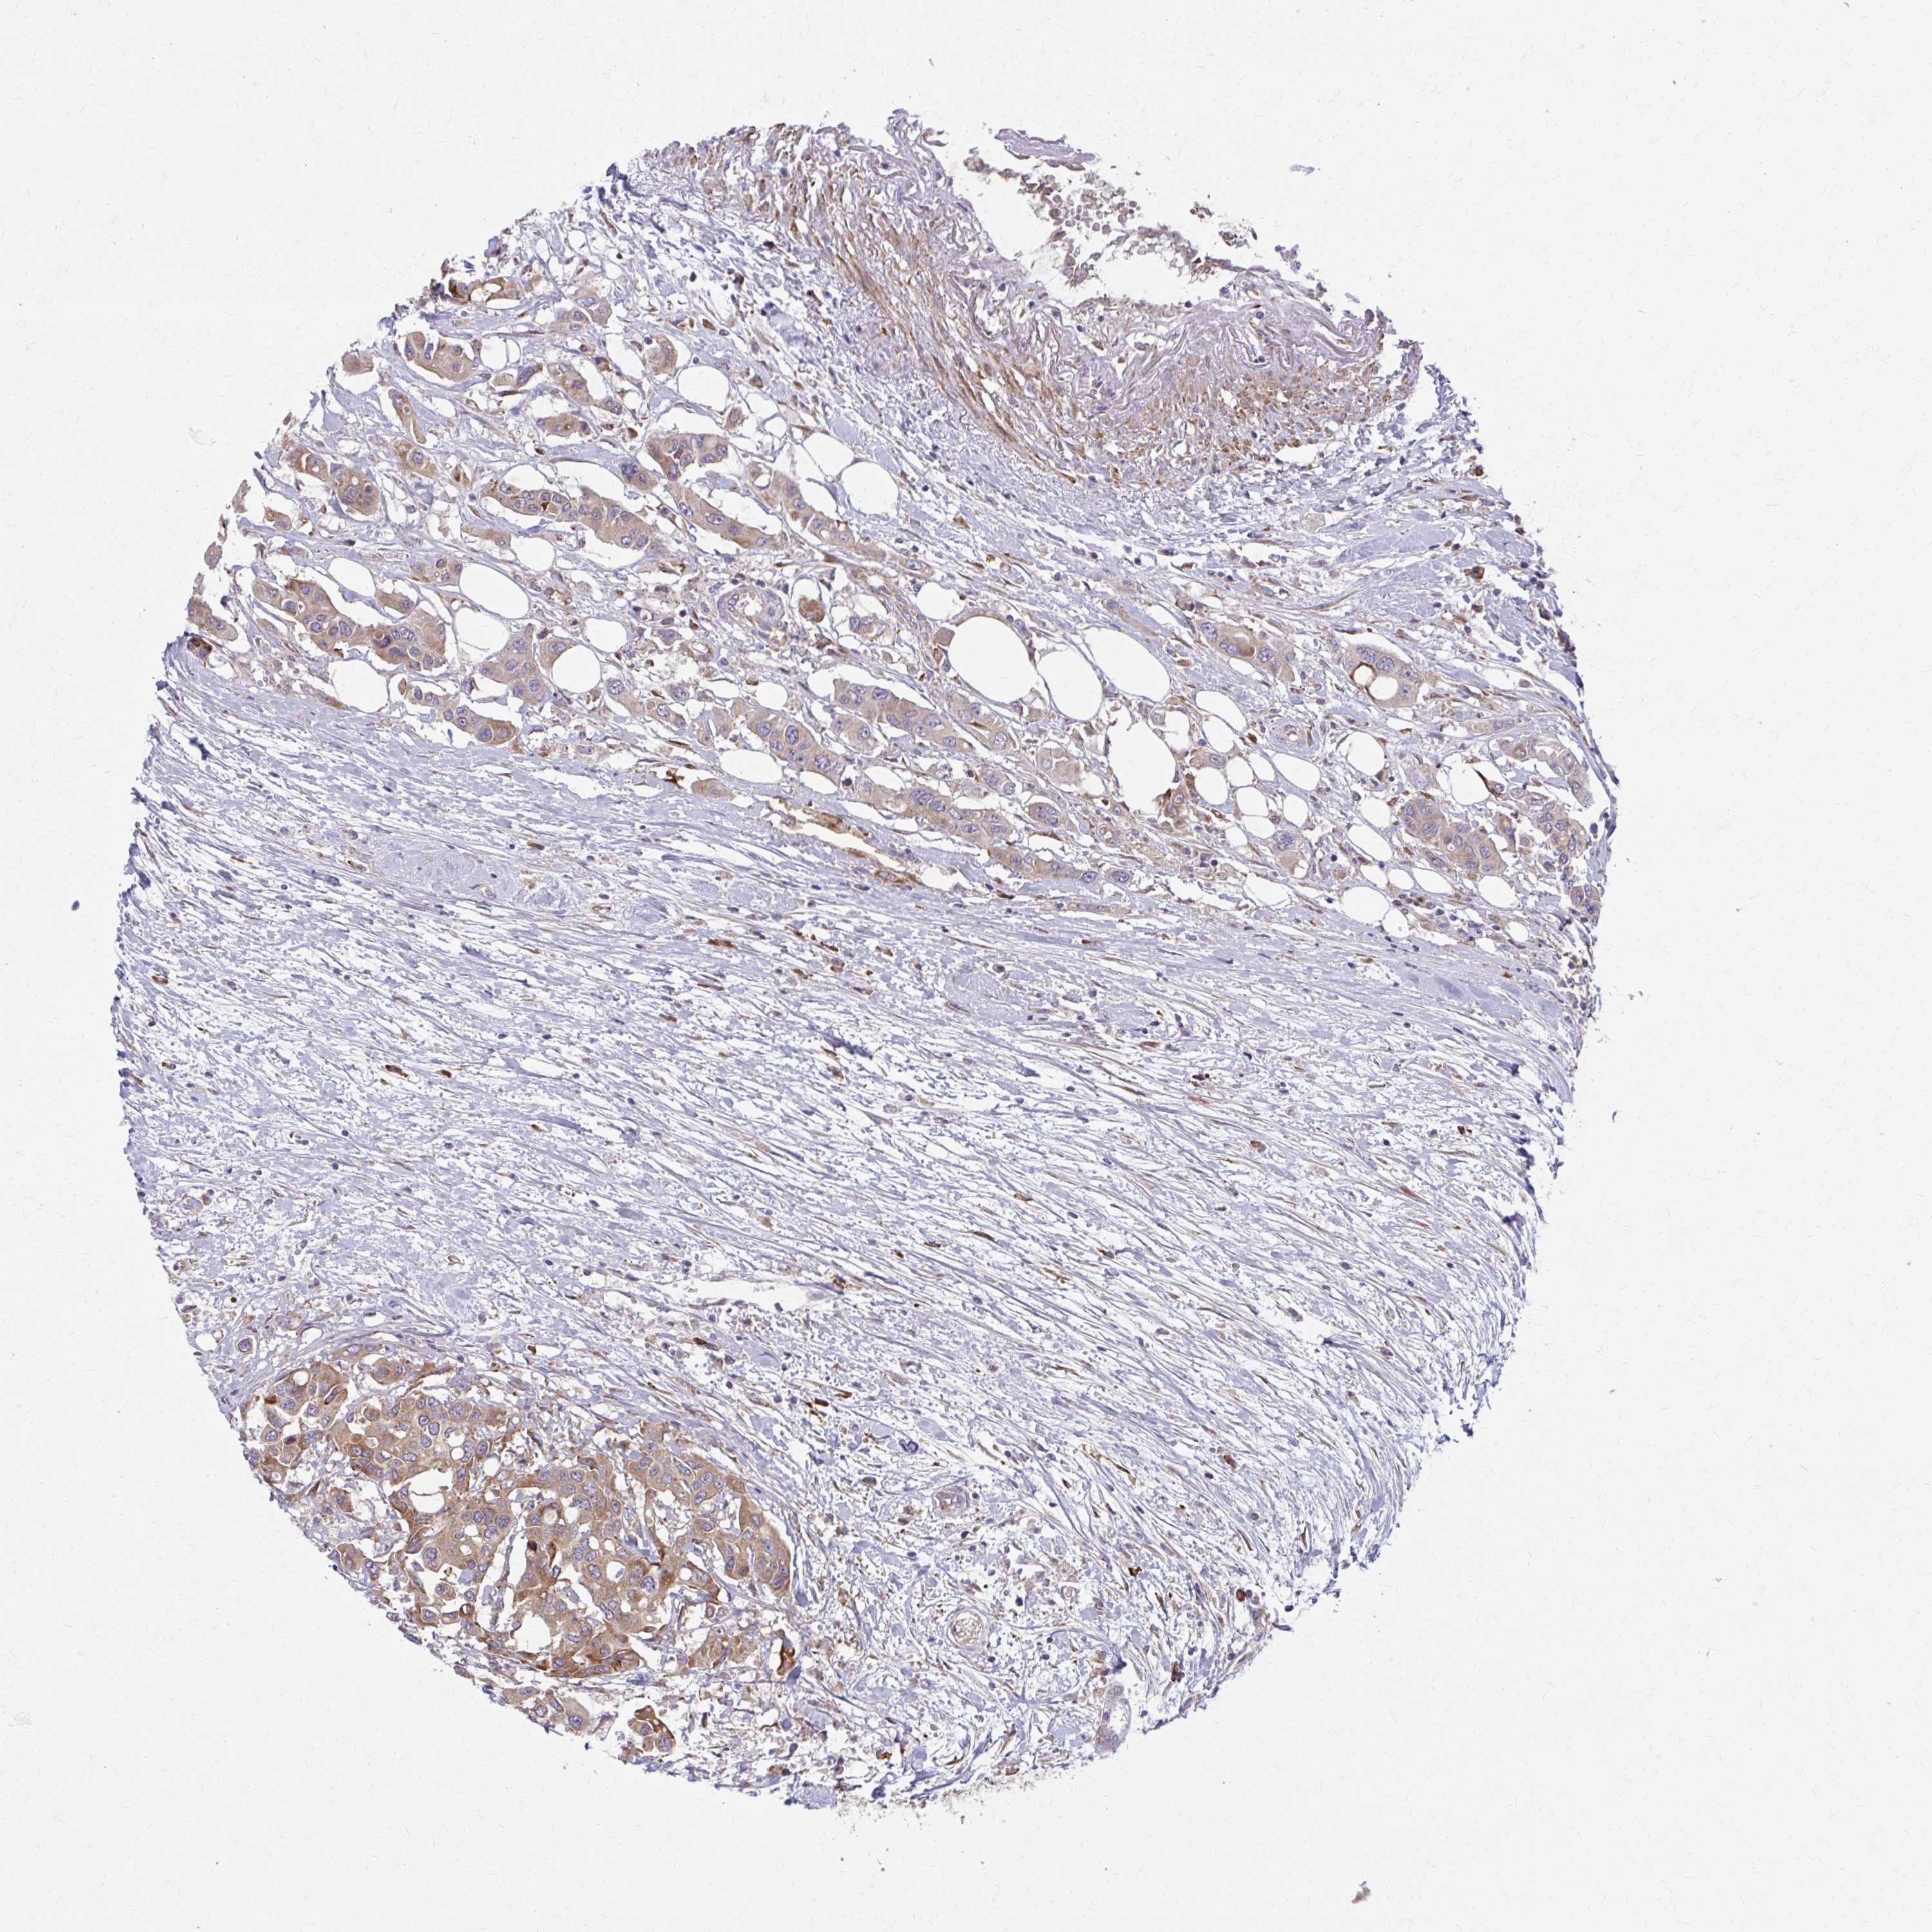

CANCER COLORECTAL CANCER Show tissue menu

Colorectal cancer

Human cancer

Colon adenocarcinoma